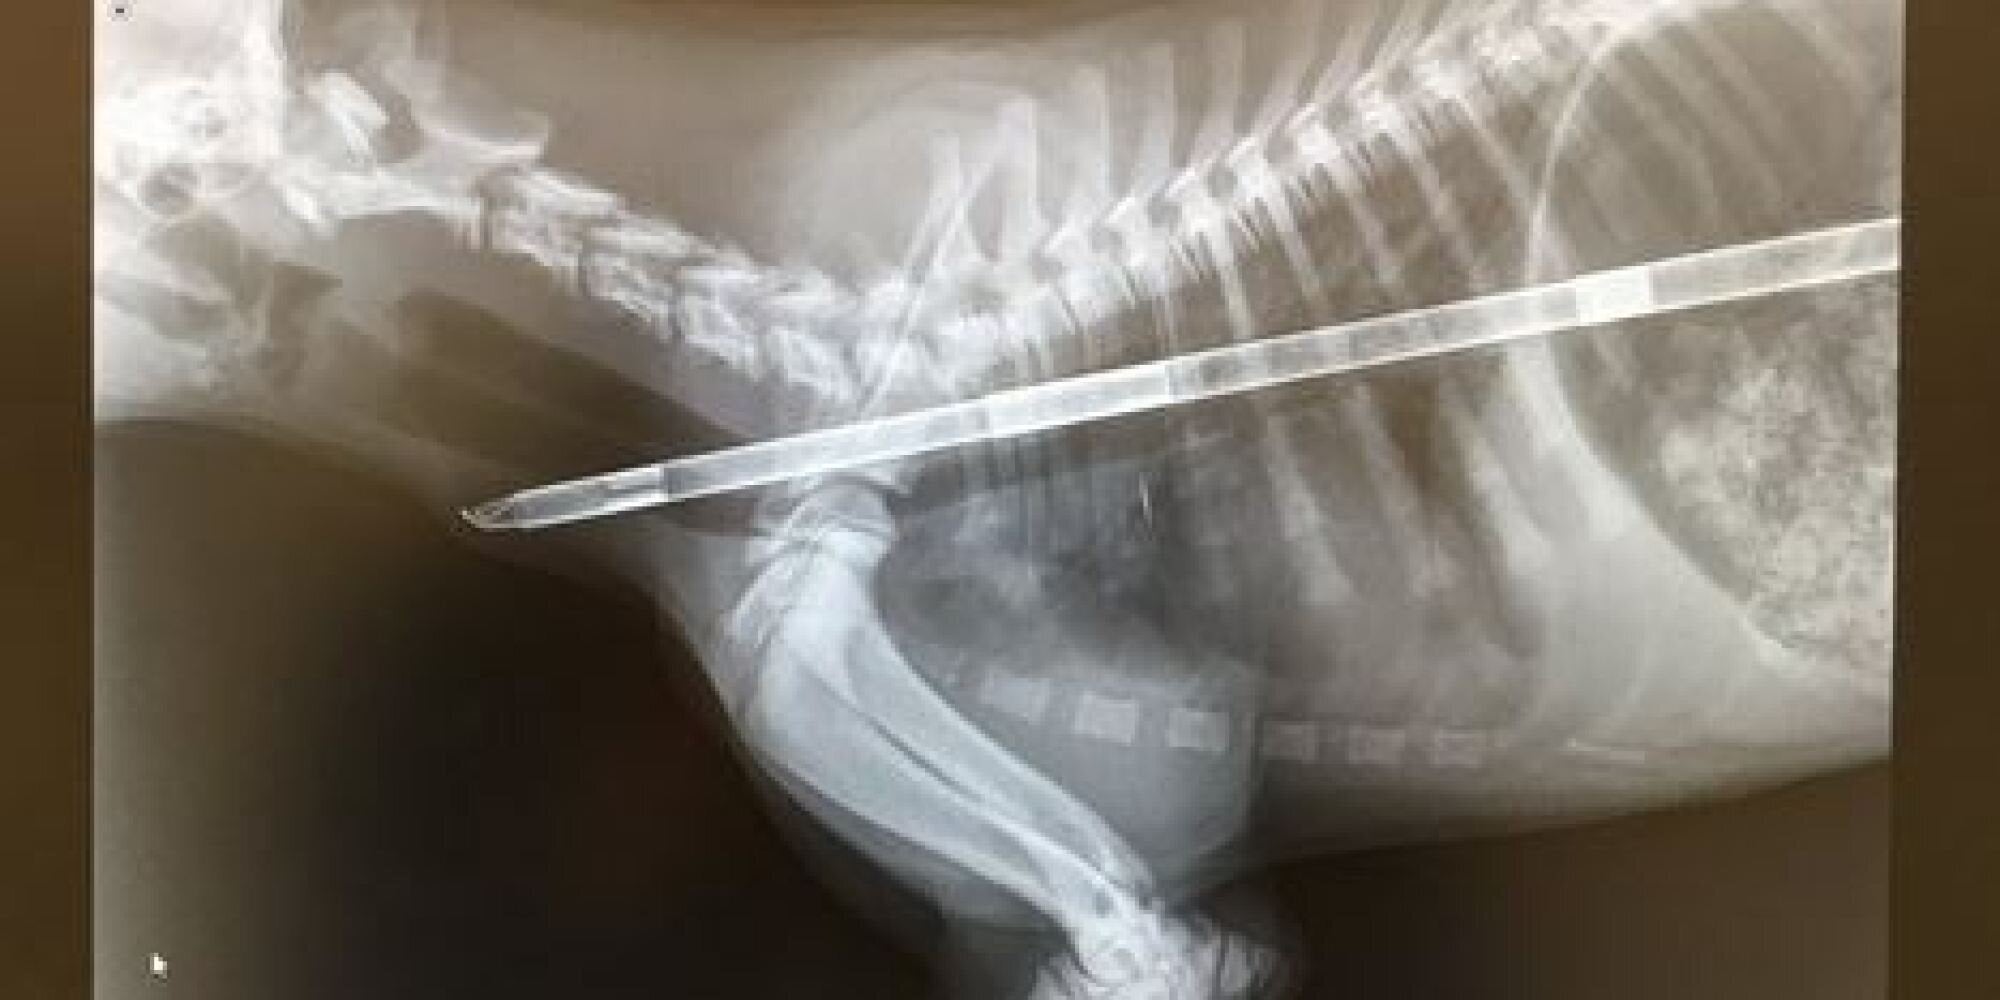

Κουτάβι κατάπιε έναν ανεμόμυλο και σώθηκε από θαύμα